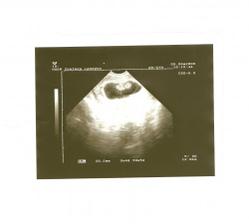

9. června - kontrola u paní doktorky proběhla bez potíží, miminko krásně roste, jsme v 8tt+4. Termín porodu je 11.1. s tím, že mám počítat o týden déle kvůlu delšímu cyklu. Odebrána krev, výsledky se dozvím za 3 týdny při další kontrole. Srdíčko bilo prostě nádherně!!! Jsem naměko 🙂 Je to fakt zázrak.